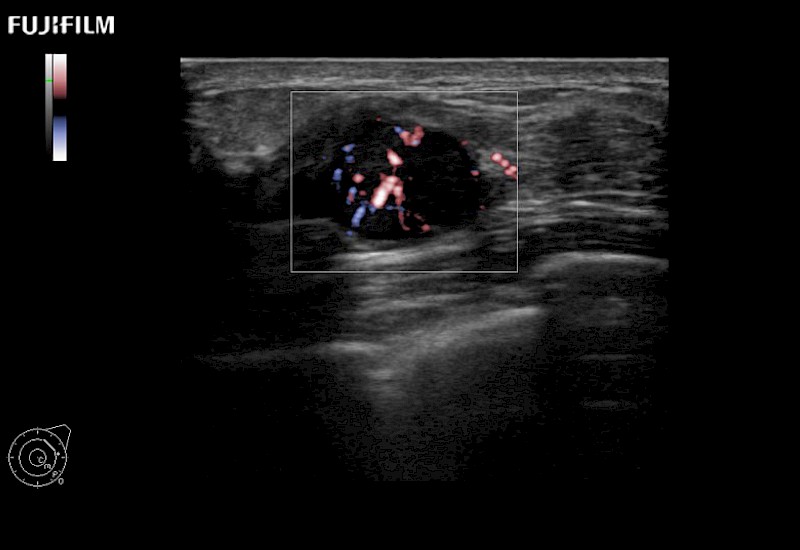

The ARIETTA 750 incorporates all of the proven technologies and functions that medical professionals have come to expect from Fujifilm Healthcare.

ARIETTA 750 is the definitive diagnostic ultrasound solution for any clinical setting - Private Office, Imaging Center, or Hospital. The ARIETTA platform provides the ultimate in clinical performance with its state-of-the-art features and large user-friendly display.

The ARIETTA 650 DI combines trusted Fujifilm Healthcare technologies and features tailored for surgical oncology.

Designed to meet the demands of surgeons, the ARIETTA 650 DI offers precise guidance. Its advanced capabilities and large, intuitive display offer accurate and efficient care in operating rooms and specialized surgical settings.